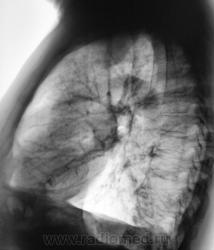

Осумкованный плеврит. Надеюсь, с ребрами там все в поряде?

Согласен но для спокойствия глянул бы на скопии.

Какие мнения будут?

Дела плевральные.Или осумкованный гидроторакс, или мезотелиома... Прошедшие годы, видимо, уже расставили точки над "i"?

Осумкованный плеврит.